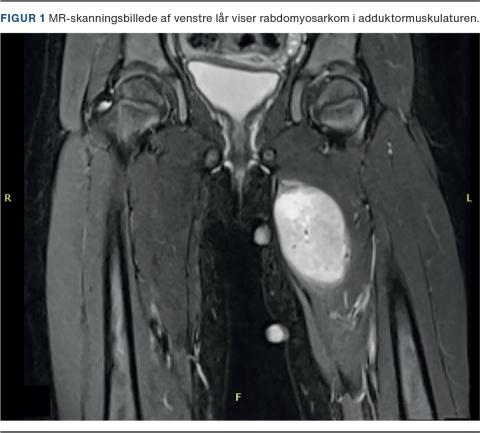

En treårig pige blev henvist til udredning for en knude på venstre lår. Den histologiske undersøgelse gav diagnosen embryonalt rabdomyosarkom. Tumoren målte 5,2 × 4,3 × 3,1 cm, og der var ingen tegn på spredning (Figur 1). Pigen blev behandlet med fire serier neoadjuverende kemoterapi, inden tumoren blev fjernet kirurgisk. Herefter blev hun behandlet med yderligere fem serier kemoterapi og overgik til sidst til 24 ugers konsoliderende kemoterapi. Fire måneder efter operationen viste en MR-skanning ingen tegn på resttumor.